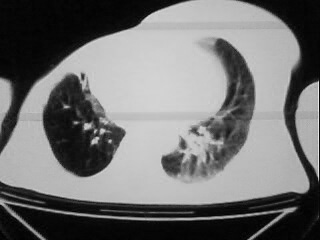

以下是引用随光逐影在2009-2-10 0:07:00的发言:[br]1)右肺放射性肺炎并节段性肺不张?请结合相关病史。2)右侧胸膜肥厚、粘连。3)心包膜增厚(或心包少量积液)。